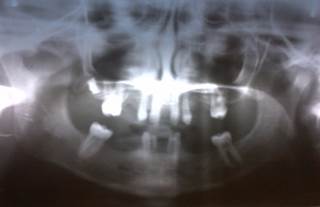

Se realizó radiografía panorámica, se siguieron las indicaciones y se cumplió con las medidas de protección radiológica para este tipo de pacientes y en la misma se observó oligodoncia de 22 dientes permanentes, y presencia de seis dientes temporales (Figura 1).

No se observó la presencia de ningún folículo intraóseo, solo 1/3 de corona del 17, por lo que se diagnostica como una oligodoncia múltiple. Los dientes que están presentes son:

Permanentes: 11, 16, 21, 26, 36 y 46.

Temporales: 53, 63, 72, 73, 82 y 8.